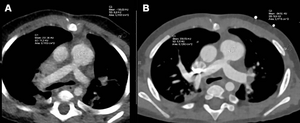

image: Cardiac photon-counting CT (PCCT) in a 174-day-old male infant with complex congenital heart defect. (A) Contrast-enhanced axial PCCT image shows sonographically suspected sinus venosus defect with partial anomalous pulmonary venous connection. (B) Contrast-enhanced coronal PCCT image. (C) Anterior view of three-dimensional reconstruction shows a partial anomalous pulmonary venous connection of two separate lung veins from the right upper and middle lobe to the right superior vena cava (red arrows) and a persisting left superior vena cava (yellow arrow). (D) Three-dimensional reconstruction, posterior view. The diagnosis was confirmed at PCCT, and PCCT allowed for visualization of the partial anomalous pulmonary venous connection of two separate lung veins from the right upper and middle lobe to the right superior vena cava. One lung vein drains correctly to the left atrium (green arrow). A sinus venosus defect, an atrial septum defect, an enlarged right atrium and a persisting left superior vena cava are shown. The only regular confluence of a single right lung vein into the left atrium is shown (D; green arrow). Image quality was rated as 5 of 5 (optimal). view more

The researchers found that the PCCT images were sharper, with less image noise and greater contrast than DSCT images. The mean overall visual image quality ratings were higher for PCCT versus DSCT at a similar radiation dose. More than 97% of the PCCT images were at least diagnostic quality, compared to 77% of the DSCT images.